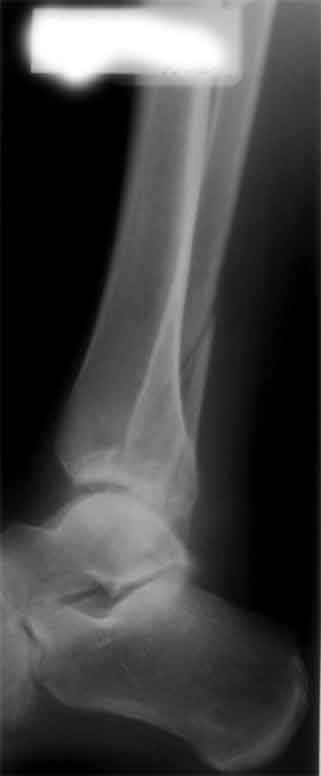

застарелое повреждение голеностопного сустава

Пациент 42 лет. обратился на консультацию с травмой голеностопного сустава через 1,5 мес после травмы, репозиция и фиксация повреждений не проводилась.

В настоящее время движения в голеностопе с амплитудой 10-15 градусов.

Интересует ваше мнение, имеет ли смысл заниматься восстановлением поврежденных структур (остеотомия м/б, остеосинтез внутренней лодыжки и т.д.) или предпочесть артродез голеностопного сустава, требования пациента не высокие, основная жалоба сейчас -боль. Более качественные снимки и проекции пока представить не получится.